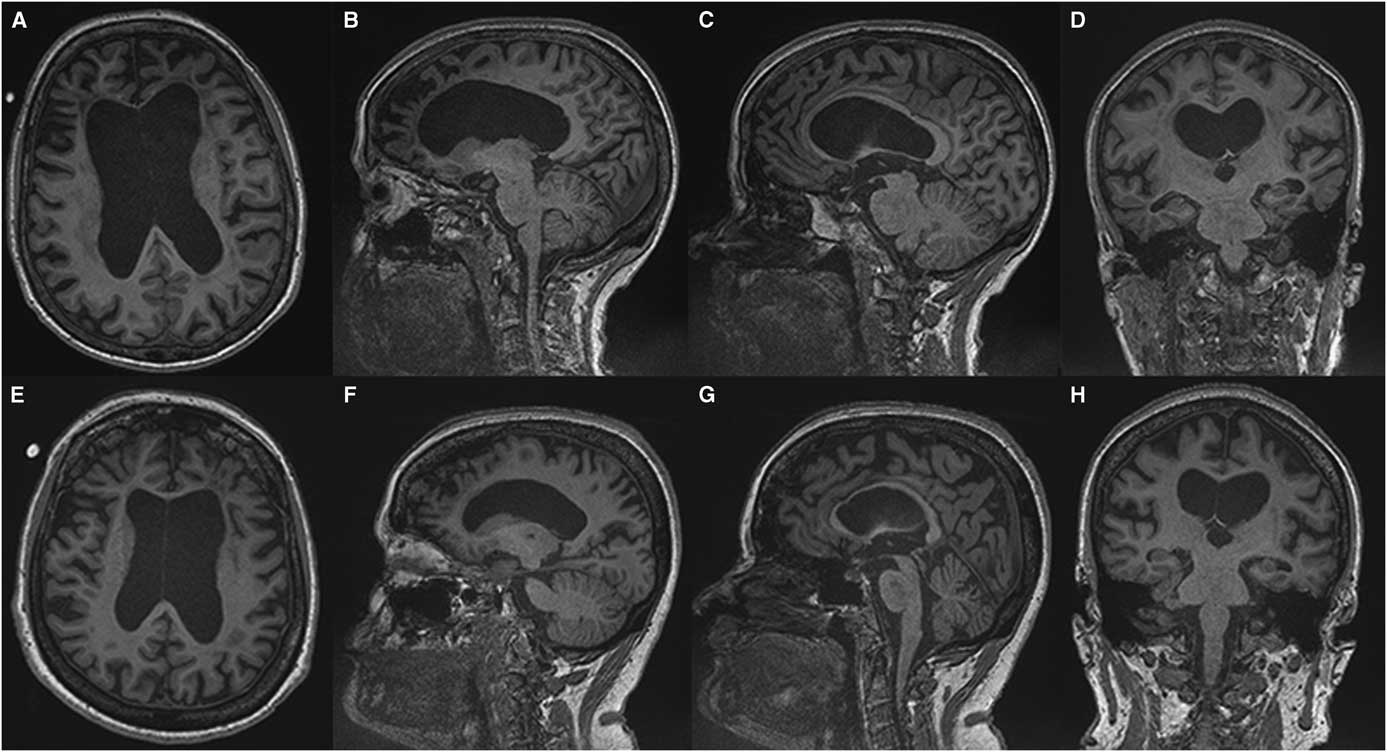

(Sachin Pandey) On axial T2-weighted MRI for patient one (Figure 1), we see some hyper-intense signal in the pons. In the middle cranial fossa, and superiorly there is severe bilateral volume loss in the hemispheres that is most pronounced in the frontal lobes. The distance of the ependymal margin of the lateral ventricles and the overlying cortex is down to a few millimetres. The ventricular calibre is enlarged, which may be germane given her mother’s history of shunt placement. There is less severe volume loss in the parietal and occipital lobes. What little frontal white matter remains is bilaterally demonstrating confluent abnormal signal indicative of underlying white matter disease. There is preservation of ganglionic volume and signal intensity. In the mid-sagittal plane, we see that the corpus callosum is markedly thinned anteriorly worse than posteriorly. There were no focal areas of cystic encephalomalacia or acute/subacute infarcts. There are no masses or foci of abnormal contrast enhancement. In summary, we see bilateral volume loss and confluence of white matter signal abnormality that are most striking in the frontal lobes, with relative preservation of the grey matter volume, and volume of the posterior fossa and brainstem. My impression is that the volume loss is predominantly because of white matter disease although there may be some degree of cortical atrophy. Furthermore, the quality and location of the white matter disease is not typical of microvascular disease. The degree and pattern of white matter abnormality was comparable between the two siblings, if not worse in patient one despite her milder clinical syndrome (Figure 2).

Figure 2 Comparing T1-weighted imaging between siblings. Patient one (A-D) presented with mild to moderate amnestic/executive complaints while patient two (E, H) presented with a rapidly progressive behavioural syndrome. Despite this discrepancy both patients demonstrate a similar degree of atrophy and subcortical volume loss in the frontal and temporal lobes with ventricular enlargement on axial (A, E) and sagittal (C, D) images. A greater burden of frontal white matter hypointense lesions is observed in patient one (A) which belies the relative severity of the her clinical syndrome. Anterior callosal thinning is seen in both patients (E, F).